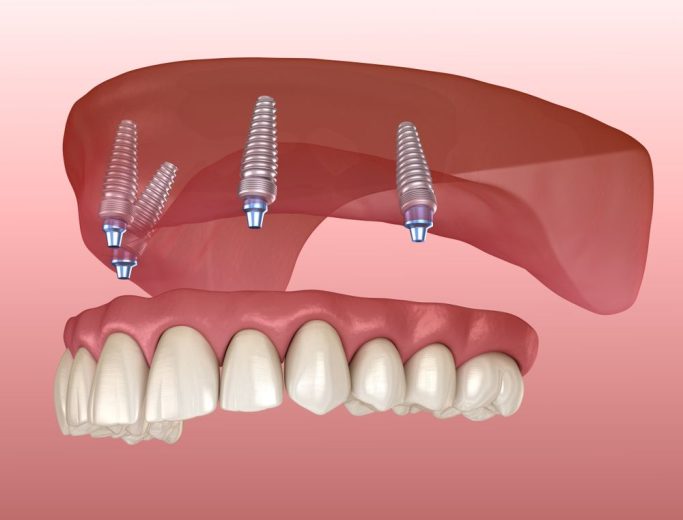

۳. کاشت پایه ایمپلنت – همان لحظه (۳۰ تا ۴۵ دقیقه)

بعد از اینکه دندان کشیده شد و استخوان آماده شد، پایه تیتانیومی در همان جلسه کاشته میشود.

۴. نصب دندان موقت — همان روز!

در این مرحله یک تاج موقت (معمولاً از جنس آکریل) روی پایه نصب میشود.

۲. حفظ زیبایی چهره

بهخصوص در دندانهای قدامی، ایمپلنت فوری باعث میشود:

- فرم لثه حفظ شود

- استخوان تحلیل نرود

- لبخند طبیعی بماند